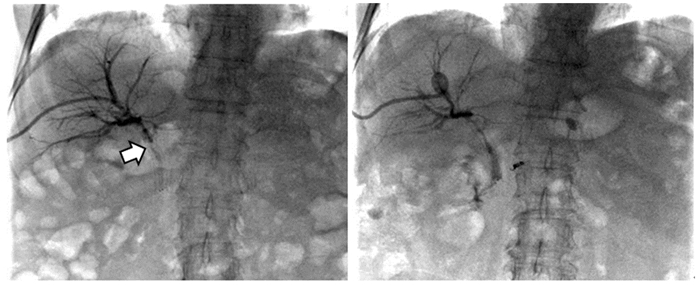

1.2.3 术后随访嘱患者避光1个月,术后1~2个月复查胆道造影,见图 1,视情况决定是否拔除胆道引流管。通过门诊定期监测肝功能,通过生化检查、胆道造影或腹部影像学检查(CT/MRCP)观察胆红素水平、胆道通畅情况。夹闭外引流管或拔除引流管后,胆红素未见进行性升高判定为胆道通畅。记录术后1、3、6和12月胆道通畅情况。

| 图 1 患者老年女性,胆道恶性肿瘤合并胆道狭窄,支架后再次出现皮肤巩膜黄染,PDT术前胆道造影见支架内充盈缺损(箭头处),对比剂无法顺利通过(左图);PDT治疗1月后再次造影见支架恢复通畅,对比剂可顺利通过并进入肠道内(右图) Figure 1 An elderly female patient with biliary malignancy complicated with biliary stricture, presented with yellow staining of skin and sclera after stenting. Biliary angiography before photodynamic therapy (PDT) showed a filling defect in the stent (arrow), and the contrast agent could not pass smoothly (left). One month after PDT, the stent was unobstructed again and the contrast agent could pass through and enter the intestine smoothly (right) |